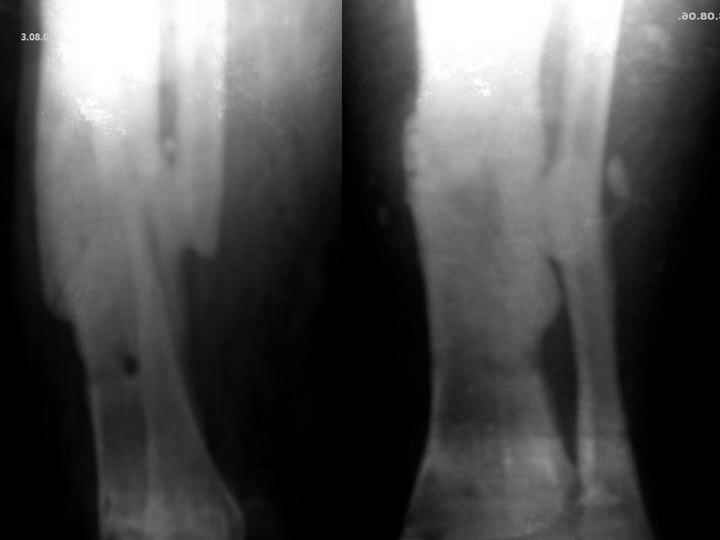

Мужчина, 29 лет. Состоит на лечении в ЦРБ.Диагноз: Замедленно сростающийся со смещением повторный перелом обеих костей левой голени вс/3-н/3, состояние после ВЧКО, хронический остеомиелит костей левой голени, свищевая форма,трофический синдром, смешанная контрактура левого коленного, голеностопного суставов.

Травма 20.12.04. - открытый 2Б тип, оскольчатый перелом обеих костей левой голени в с/3-н/3 сосмещением отломков (ДТП). 20.12.04.- ВЧКО костей голени АВФ спице-стержневого типа, ПХО ран.Лечился амбулаторно. Перелом длительно не сростался. АВФ демонтирован 22.06.05., разрешена нагрузка на ногу, после чего появилась подвижность в области перелома. 8.07.05. - ВЧКО, туннелизация по Беку. Течение осложнилось развитием спицевого остеомиелита, 1.11.05. АВФ демонтирован, получал консервативное лечение. После нормализации состояния 17.11.05.- секвестрэктомия, ВЧКО голени.12.04.06. АВФ демонтирован.

3.06.06.повторная травма - закрытый повторный перелом левой б/б кости в с/-н/3, лечился методомгипсовой иммобилизации.

Место болезни - ось голени искривлена. Kеллоидные рубцы в местах проведения спиц, по передней поверхности голени. По передней и внутренне-боковой поверхности голени в определяется 3 свища с умеренным серозным отделяемым. Отек голени и сустава, движения в коленном и голеностопном суставах ограничены, неврологических расстройств в стопе нет.

Снимки, конечно, оставляют желать. Ладно, пробуем предложить решение в условиях недостатка информации. В том числе не зная о доступных на месте методах лечения.

Если первое - снова остеосинтез аппаратом, остеотомия малоберцовой кости, дозированное исправление оси и длины.

Если инфицированный ложный сустав - лучше перевести пациента в более оснащенное чреждение.

Здравствуйте!IMHO:хороший дебридмент,бусы с а\б,обязательно АВФ для исправления оси.Возможно,конечно,резецировать пораженный участок,компактотомия в\3 б\берца с остеотомией м\берца в с\3 и по Илизарову...Долго,конечно,но эффективно.Ну и спейсер можно поставить интрамедуллярно(со спицей)на4-6 недель